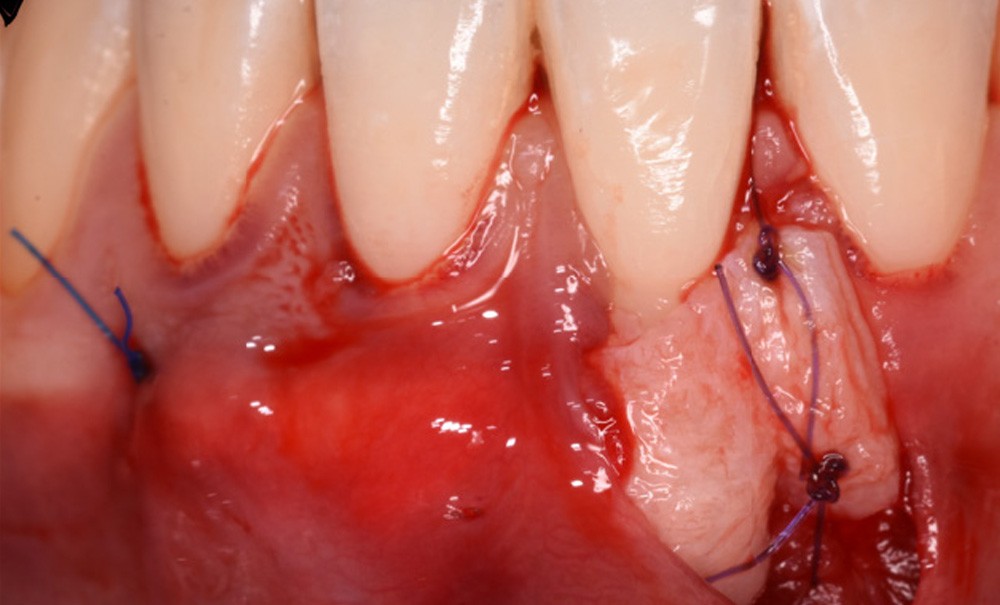

Nous présentons ici une série de cas de récessions unitaires mandibulaires traités par la technique TCAF, combinant un lambeau avancé coronairement (CAF) et un tunnel modifié (TUN) avec greffon conjonctif enfoui (Tavelli et Barootchi, 2022).

30 patients présentant une récession gingivale (RT1 ou RT2) affectant une incisive mandibulaire ont été inclus. Une chirurgie de type lambeau tunnelisé et avancée coronairement (TCAF), associée à un greffon conjonctif, a été réalisée selon la technique décrite par Tavelli et Barootchi (2022). Le critère principal, à 6 mois après l’intervention, était le recouvrement moyen de la récession (en millimètres et en pourcentage). Les critères secondaires, également évalués avant et 6 mois après la chirurgie, comprenaient : le recouvrement total (100 %), la hauteur de tissu kératinisé (en mm) apicalement à la récession et le score esthétique de recouvrement radiculaire (RES).